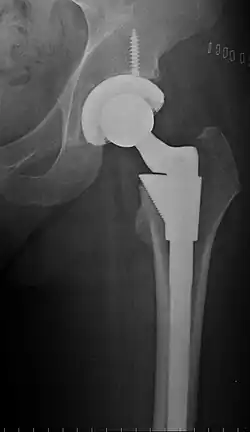

Metal on metal prosthetic hip

Cement-free implant sixteen days after surgery. Femoral component is cobalt chromium combined with titanium which induces bone growth into the implant. Ceramic head. Acetabular cup coated with bone growth-inducing material and held temporarily in place with a single screw.

The prosthetic implant used in hip replacement consists of three parts: the acetabular cup, the femoral component, and the articular interface. Options exist for different people and indications. The evidence for a number of newer devices is not very good, including: ceramic-on-ceramic bearings, modular femoral necks, and uncemented monoblock cups.[90]